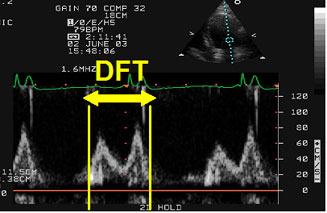

Figure 1

Atrioventricular asynchrony assessment. DFT: diastolic filling time measured with PW - Doppler in the 4-chamber apical view as the time passed from the beginning of the E wave to the end of the A wave. Atrioventricular asynchrony is described if the DFT is < 40% of the cardiac cycle.

It can be echocardiographically evaluated by measuring the LV filling pattern with Pulsed-Wave (PW) Doppler, which obtains the E wave, that represents the passive LV filling, and the A wave, that shows the LV filling due to the atria contraction.

Atrioventricular asynchrony is defined as the presence of a LV diastolic filling time shorter than 40% of the cardiac cycle as shown in Figure 1. The maximal expression of AV asynchrony is the presence of atria fibrillation, when atria contraction, on the other hand very reduced, occurs independently of LV mechanics.